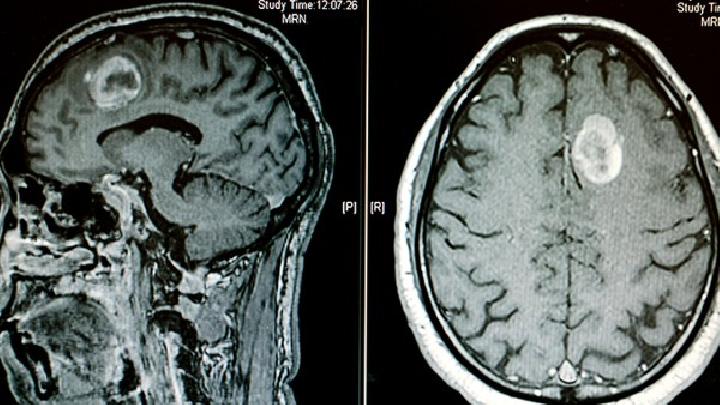

(7)头CT扫描检查,挫伤区呈片状高密度影。可伴有脑水肿或脑肿胀,也可伴有颅内血肿和创伤性蛛网膜下腔出血。

1、CT

对于急性脑损伤的常规检查,如果病情允许,首先考虑急诊头颅CT。可发现脑混合裂区有点片状高密度出血炉,或高密度和低密度混合区。脑水肿区域为低密度阴影,可显示大脑压力变形和位移。创伤性蛛网膜下间隙出血,在CT也可以在图像中检测到,表现为脑池、脑沟等不规则。